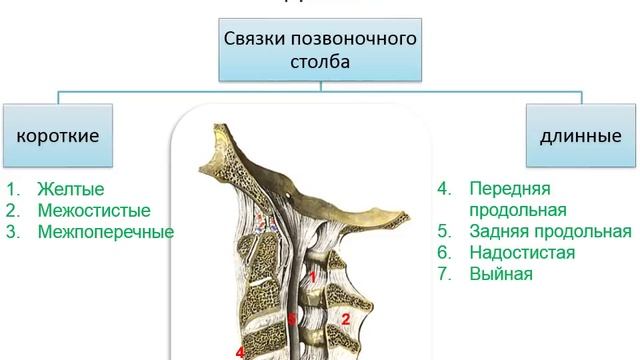

Структура и анатомия синдесмоза: научные иллюстрации